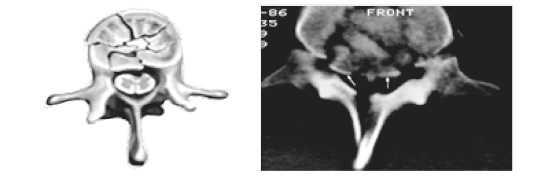

1.X线片示T11椎体爆裂骨折。

2.腰椎CT示T11椎体爆裂骨折,椎管内占位性病变。诊断为T11椎体爆裂骨折并脊髓损伤。

患者腰椎CT